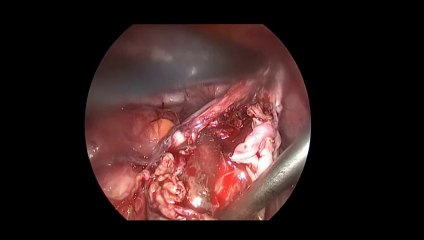

Laparoskopi ile Endometiroma (Çikolata kisti) operasyonu 1 - Prof. Dr. Aydan Biri

Laparoskopi ile Endometiroma (Çikolata kisti) operasyonu 1 - Prof. Dr.